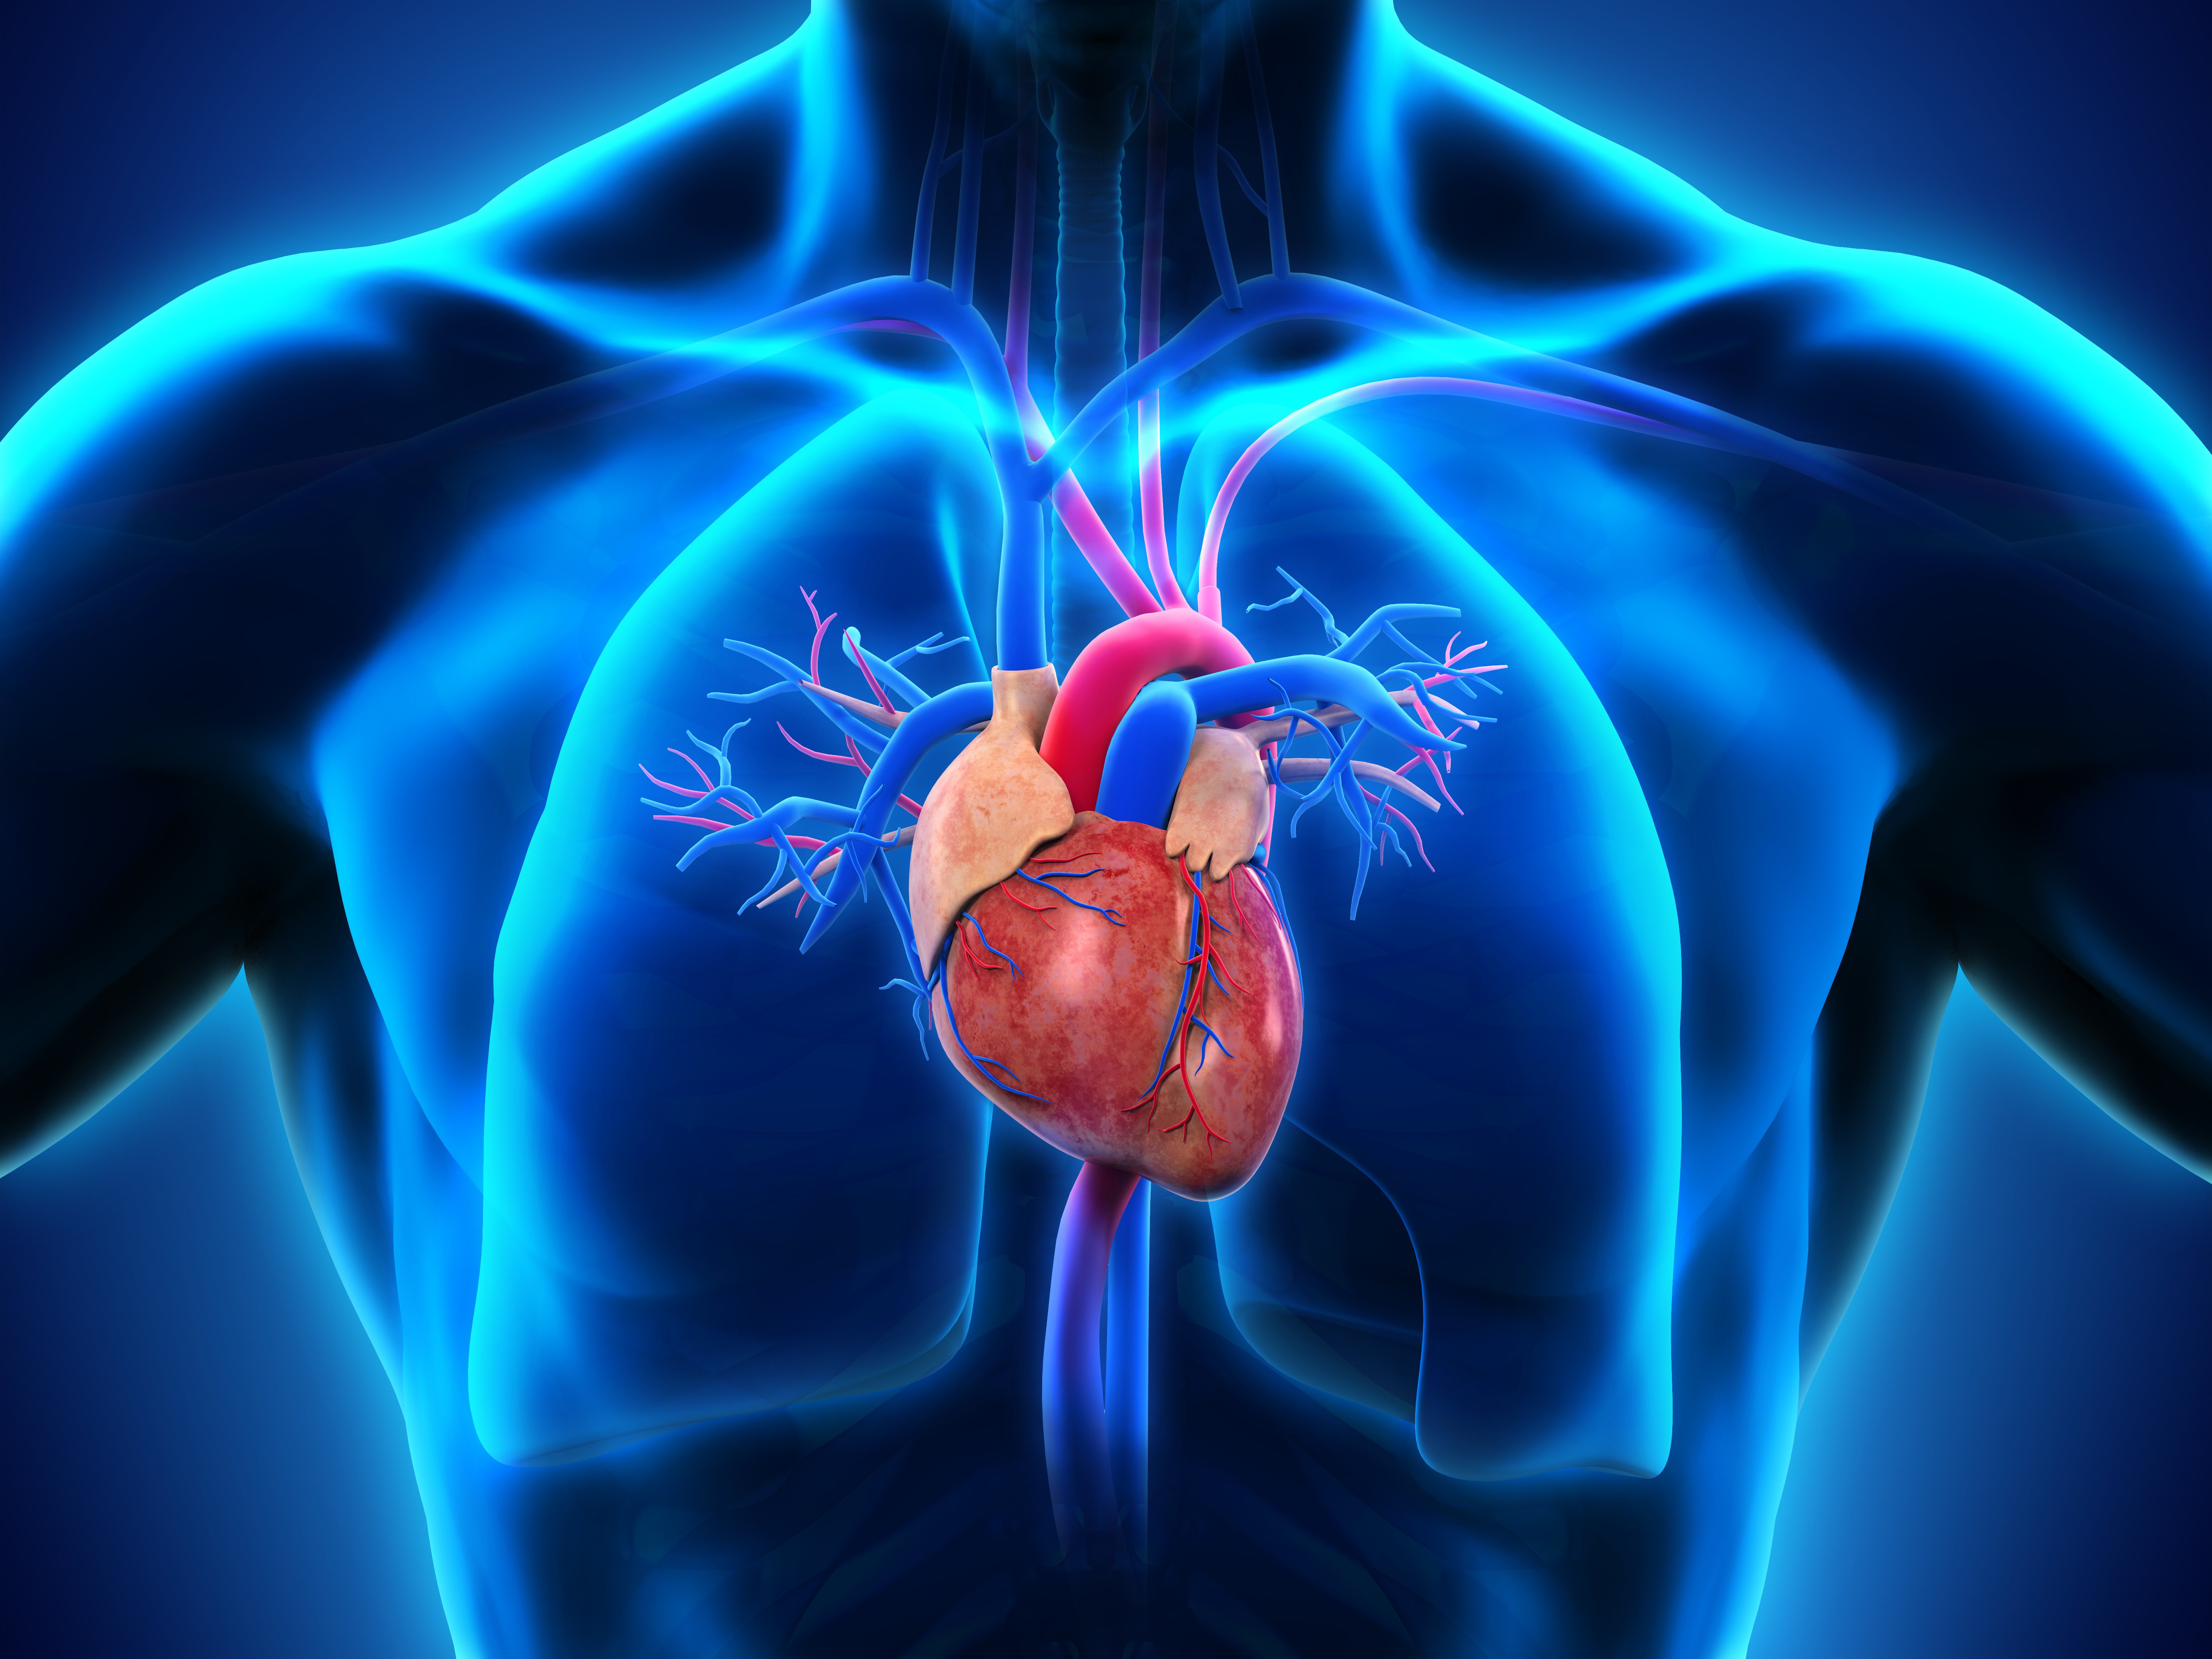

Анатомия здорового сердца: фотографии и иллюстрации

Раздел: Лаборатория идей